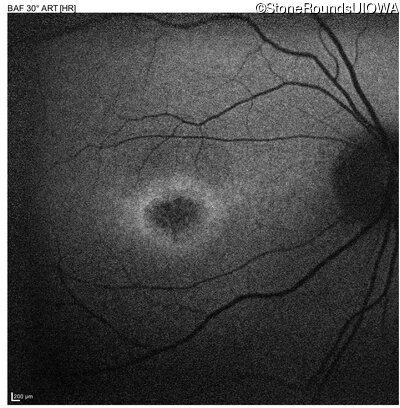

AR Stargardt Disease (IIA)

Age at visit:

15 years

OD

OS

20/125 -1

20/80

AR Stargardt Disease

ABCA4

Val256Val GTG>GTT

Gly1961Glu GGA>GAA

AR